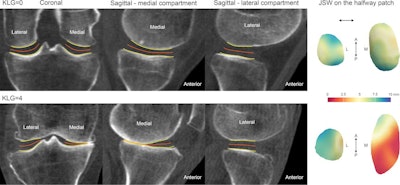

In addition, statistical parametric mapping performed on 33 individuals revealed that the central-to-posterior medial joint space was significantly narrower by 0.5 mm (threshold p < 0.05) for each incremental increase in the patient's Kellgren-Lawrence grade.

Also, one patient with a Kellgren-Lawrence grade of 2 had a 24-month change in a patient's 3D joint space width distribution that was beyond the smallest detectable difference across the lateral joint space, according to the researchers.